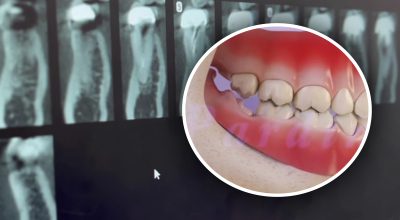

"Зуб мудрості" - восьмий зуб зверху (і знизу) названий так тому, що починає рости у віці від 17 до 25 років (коли, вважається, людина стає "мудрою"). Однак існують і винятки, наприклад, коли зуб мудрості лізе у 45 років.

Це останні зуби в ряду щелепи, тому їх так складно рвати, а ще важче - реабілітація після хірургічного втручання.

Зуб мудрості - симптоми, які змусять вас піти до лікаря

Якщо ви помітили у себе відразу кілька збігів за вказаними симптомами, краще відразу ж записатися до лікаря:

- Біль, що тисне у зубах під час жування;

- набряк і запалення ясен навколо зуба;

- кровотеча ясен під час чищення зубів;

- ріжучий біль у зубі від холоду, солодкого або гарячого;

- біль у вухах і горлі;

- біль у шиї та щелепах;

- зубне "зрушення".

Крім того, коли болить зуб мудрості, є великий ризик його зараження від залишків їжі. Адже ці зуби дуже важко чистити через їхнє складне розташування.